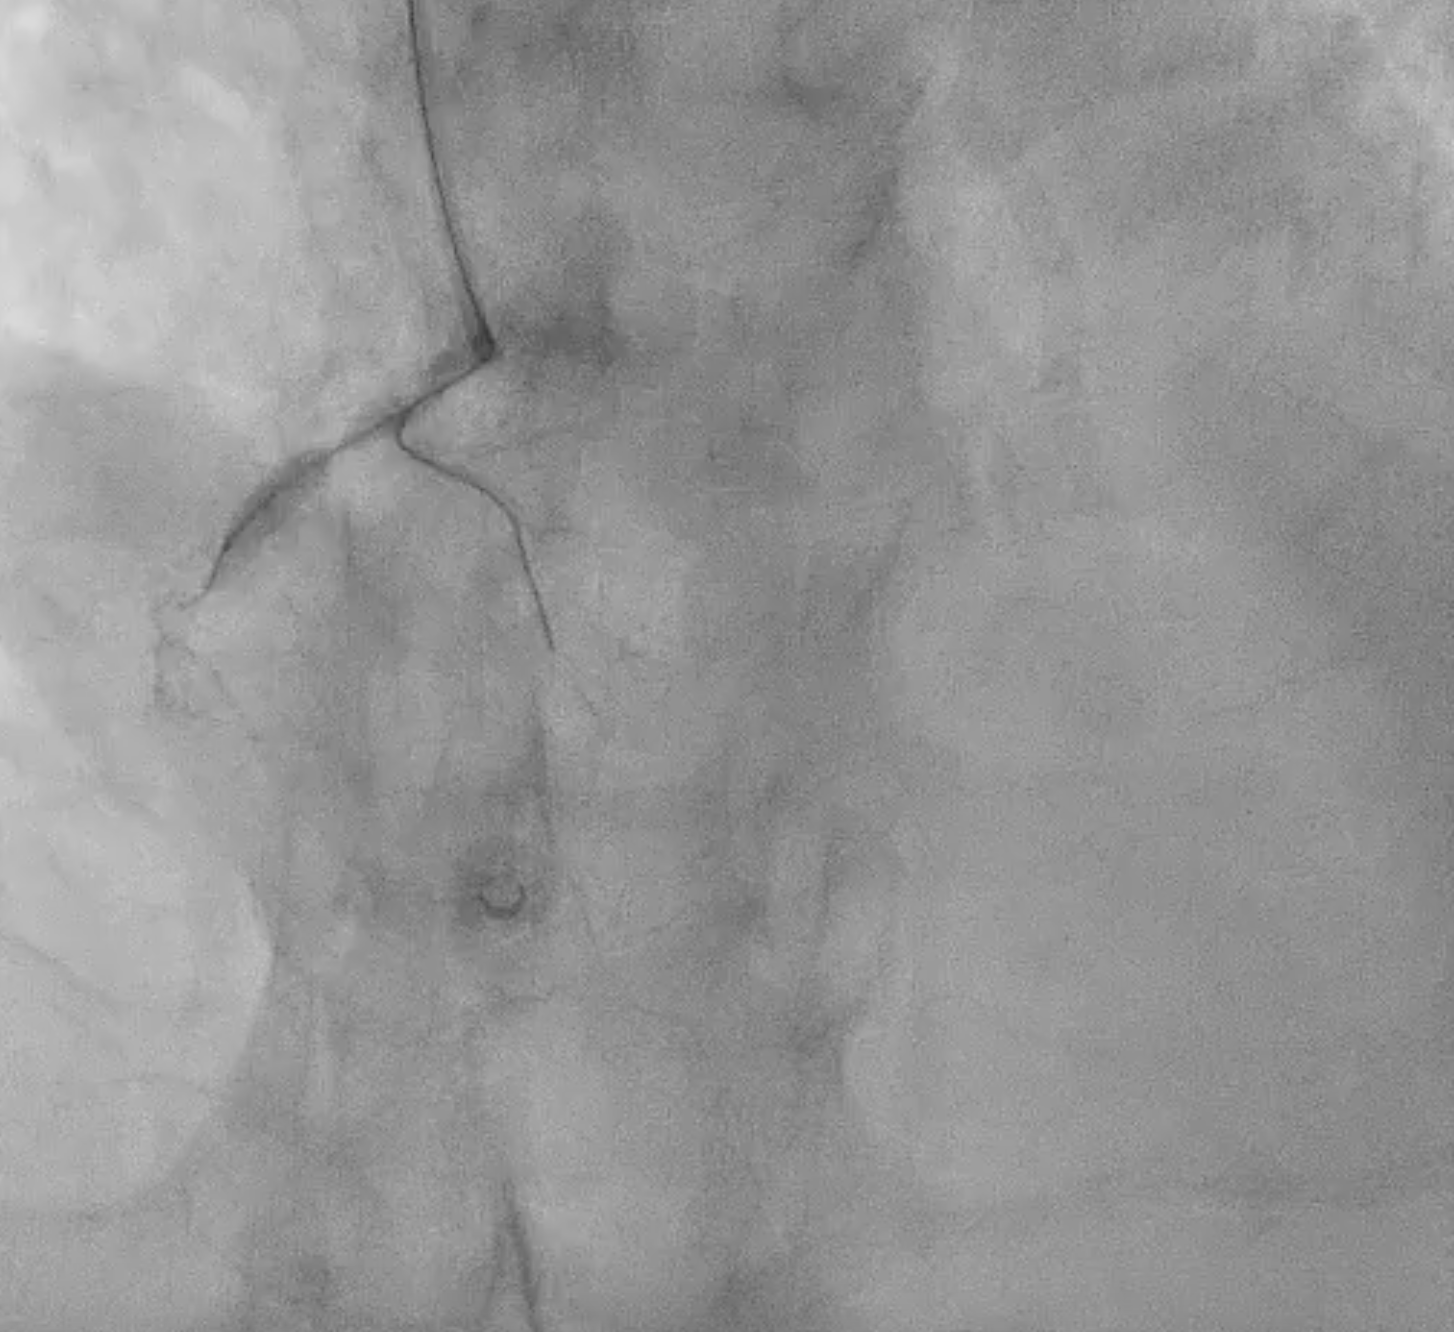

Coronary angiography revealed three-vessel disease (SYNTAX score 29) with total occlusion of the proximal to mid LAD, 50% stenosis at the proximal LCX, and 70% stenosis at the distal LCX. The RCA showed chronic total occlusion from the proximal segment with collateral filling from both the LCX and LAD. The findings were consistent with acute anterior STEMI.

Because the patient presented with acute coronary syndrome, primary PCI was first performed for the culprit lesion, and a drug-eluting stent (DES) was implanted in the proximal LAD. A staged PCI with DES implantation to the proximal LCX was later performed. The initial antegrade attempt for RCA chronic total occlusion (CTO) failed despite wire escalations, as the guidewires could not cross the lesion. Considering the patient¡¯s intolerance and high contrast volume, the procedure was terminated. One month later, the patient was readmitted for complete revascularization. Antegrade wiring with a microcatheter and multiple guidewires (Fielder FC, ULTIMATEbros3, Conquest Pro) again failed to cross the RCA CTO. A retrograde approach using a SION wire via a septal collateral successfully reached the distal RCA. As the retrograde wire could not smoothly re-enter the true lumen, an antegrade wire was used to create a controlled subintimal hematoma, followed by the reverse CART technique. Anchoring balloon support then facilitated microcatheter advancement into the proximal RCA. The rendezvous technique achieved externalization with an ASAHI RG3 330 cm wire, and two Runthrough wires were advanced antegradely into the PDA and PL branches. After sequential balloon dilatation, two DESs (XIENCE Skypoint 2.75 ¡¿ 48 mm and 3.5 ¡¿ 38 mm) were deployed from the distal to the ostial RCA under IVUS guidance. Final angiography showed successful recanalization with TIMI 3 flow.